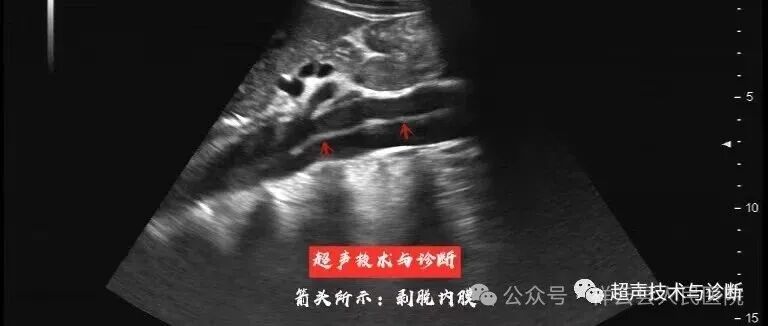

医 讯 yixun 1月10日,昆明医科大学第一附属医院心血管超声专家陈洪艳、杨娇娜将到祥云县人民医院开展诊疗活动。 坐诊时间 2026年1月10日(周六) 坐诊地点 门诊三楼超声科 诊疗范围 血管超声(颈动脉、下肢动静脉、上肢动静脉、血液透析通路建立前后的超声评估等血管疾病) 咨询预约方式 杨江瑶 15368725688 专家介绍 陈洪艳 副主任医师 昆明医科大学第一附属医院超声科血管组组长。 社会任职:中国超声医学工程学会颅脑血管超声专业委员会常务委员、中国超声医学工程学会腹部超声专业青年委员、中国超声医学工程学会眼科超声专业青年委员、云南省医院协会超声医学分会委员、云南省女医师协会介入超声专业常务委员、云南省女医师协会心血管分会委员 杨娇娜 主治医师 昆明医科大学第一附属医院超声科主治医师。 擅长:血管动静脉内瘘的术前术后评估,慢性下肢静脉功能不全评估,外周血管狭窄评估。 科普知识 众所周知,血管包括动脉和静脉。如果把血管看成是水管,那么动脉就是进水管,静脉就是排水管。动脉可以把富含营养物质的动脉血输送到身体的各个角落,而静脉则把含有代谢废物的静脉血送到肝脏处理后,回到心脏,经过肺的气体交换,重新成为动脉血(下图红色为动脉,蓝色为静脉)。 因此血管外科的疾病主要包括了动脉疾病和静脉疾病。根据病变性质的不同,动脉疾病又分为扩张性疾病和狭窄性疾病;静脉疾病又分为阻塞性疾病和反流性疾病。此外,对于因血管结构异常导致的血管瘤、血管畸形和动静脉瘘也是血管外科的诊疗范围。接下来,我们详细说说不同类型的血管疾病。 常见血管疾病分类及核心特点: 动脉疾病:血流“供不上”或“破了” 1.下肢动脉硬化闭塞症 中老年人高发,因动脉粥样硬化导致下肢动脉狭窄/堵塞,典型表现为“间歇性跛行”(走路时腿酸胀疼痛,休息后缓解),严重时可致足趾坏死。 2.主动脉夹层 致命性急症,多因高血压控制不佳导致主动脉内膜撕裂,表现为“胸背部撕裂样剧痛”,需紧急救治。 3.腹主动脉瘤 主动脉局部扩张成“瘤样”,早期无症状,破裂时突发腹部剧痛、休克,被称为“腹中定时炸弹”。 4.急性动脉栓塞 多由心脏血栓脱落堵塞外周动脉,突发下肢冰凉、麻木、疼痛、无法活动,需6-8小时内取栓,否则可能截肢。 静脉疾病:血流“回不去”或“堵了” 1.下肢静脉曲张 最常见表现为小腿“青筋凸起、扭曲”,常伴酸胀、沉重,长期可引发皮肤色素沉着、溃疡(“老烂腿”)。 2.下肢深静脉血栓形成(DVT) 久坐、术后、长期卧床者高发,血栓堵塞深静脉,导致下肢迅速肿胀、疼痛,最危险的并发症是血栓脱落引发“肺栓塞”(突发胸痛、咯血、呼吸困难,致命)。 其他常见疾病 颈动脉狭窄:多由动脉粥样硬化引起,狭窄严重时可能导致脑供血不足,增加脑梗死风险。 如您有以下情况请联系我们: 1.突发的胸腹部撕裂样疼痛:主动脉夹层可能: 2.腹部的搏动性包块:腹主动脉瘤可能; 3.突发的下肢疼痛、发凉:下肢动脉栓塞可能; 4.顽固性高血压:肾动脉狭窄可能; 5.突发的晕厥、反复发作的脑梗:颈动脉狭窄、锁骨下动脉狭窄可能; 6.突发的下肢肿胀:深静脉血栓形成可能; 7.间歇性跛行、下肢溃疡、坏疽:下肢动脉硬化 8.下肢静脉血管迂曲扩张:下肢静脉曲张、髂静脉压迫综合征、血栓形成后综合征等可能; 9.需要化疗、长期肠外营养、血透的患者。